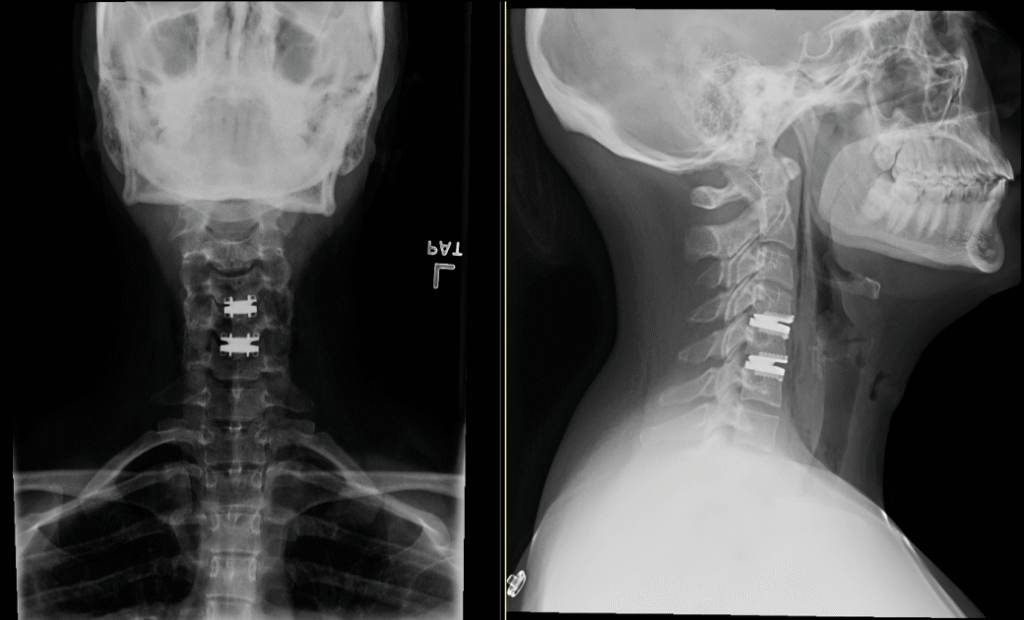

Cervical Disc Replacement

TDR 1024x626

Screen Shot 2017 08 31 At 11.02.09 PM 1024x620

Hybrid Surgery

hybrid